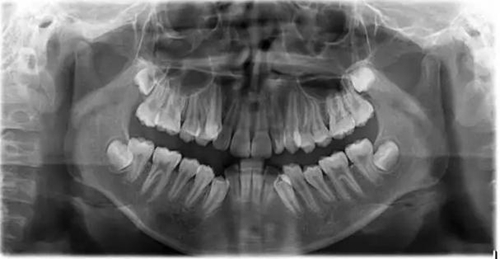

1500865770_445373.jpg1500865976_358577.jpg

此病例主要考慮的是擁擠度,磨牙及尖牙關(guān)系,前牙覆合覆蓋,生長潛力和智齒。